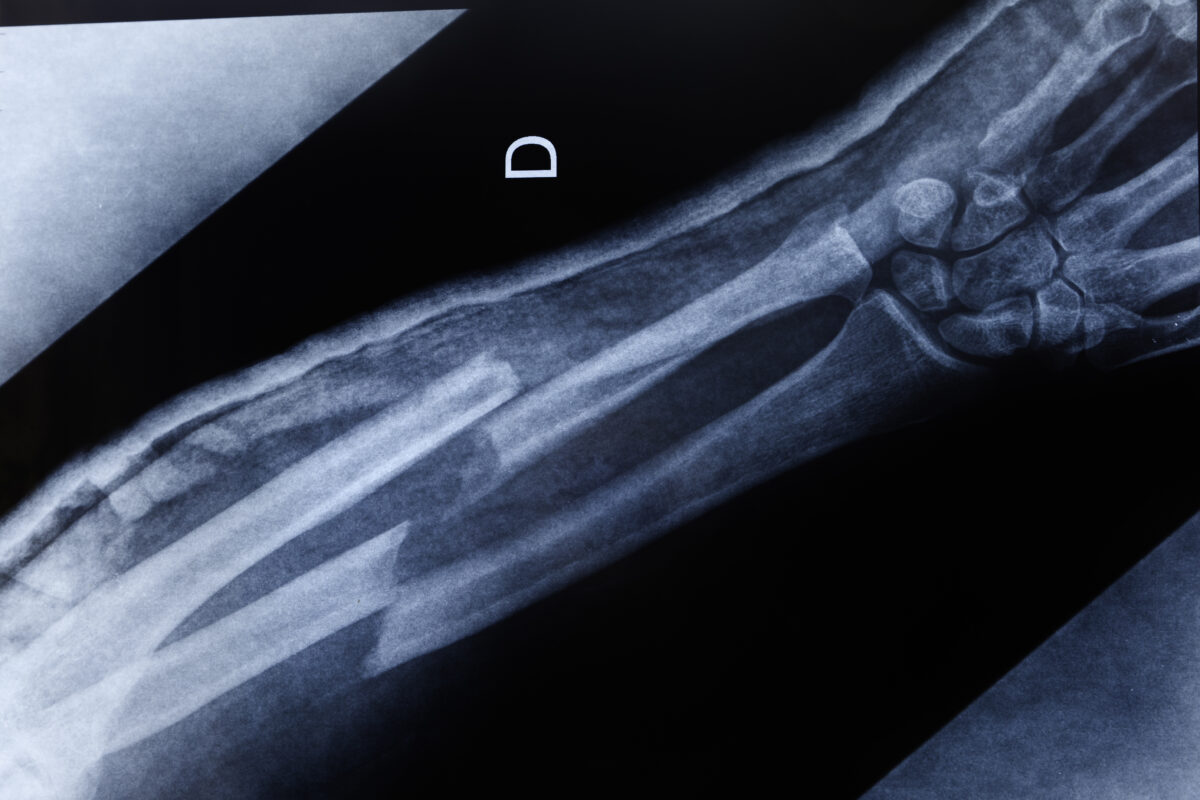

• Your orthopedic specialist may use a radiology exam to determine whether a bone is broken or a joint is damaged.

• Radiology exams can also be used to diagnose arthritis and other diseases.

• Today, digital radiology exams are used more often than traditional film radiology exams because they use less radiation and they can be viewed on a computer screen, which offers more opportunities to clearly view the picture.